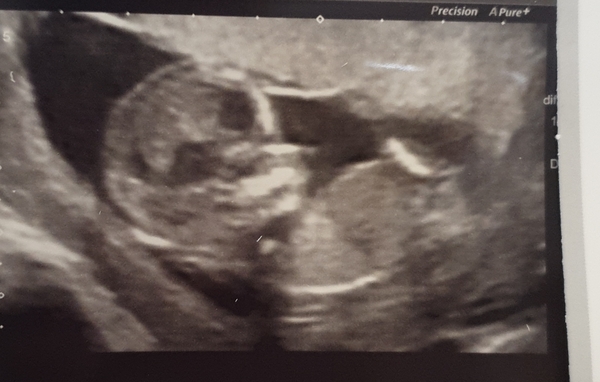

Good news here! The nuchal measurement was 1.7mm. My little boy with the chromosomal issue had a nuchal of 5.3mm.

Due date moved 3 days back to 7th September.

7th october even!